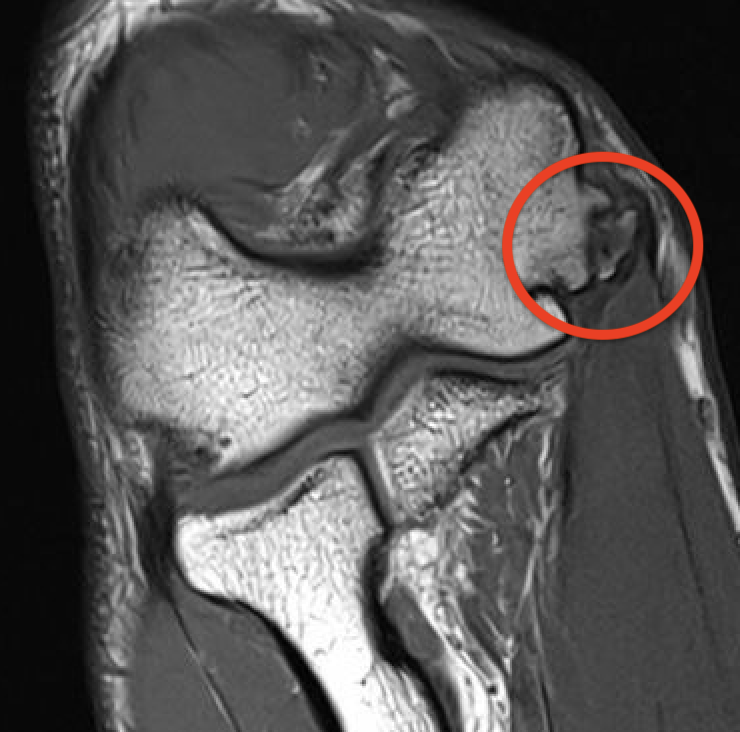

MRI

High grade partial distal UCL tear